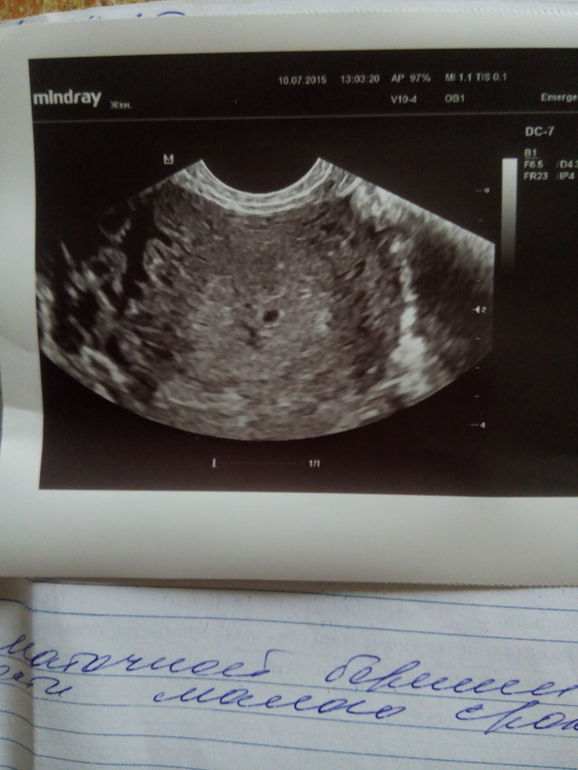

Девочки, спасибо что были рядом,)))))) Сегодня не выдержала пошла на узи, хотя нужно было только в понедельник))) УУУУУРРРРАААА !!!!! НАШЛИ МОЮ БУСИНКУ, МЫ 4 мм. Солшышко моё, как же я ждала когда тебя увижу!!!!!! Плачу)))))) От счастья конечно! Да ещё у мужа сегодня юбилей, вот и подарочек долгожданный!!!!!)))))) Я так рада, словами не передать!!!!!

Узи через 3 дня,,, вот она моя БУСИНКА

Я просто реву от радости....